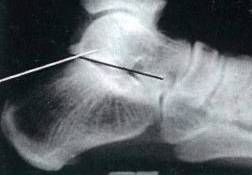

昨天做一例跟骨骨折

201752110265065173_看图王.jpg

微信截图_20160914113859.png